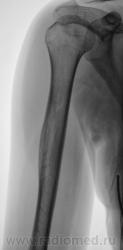

Пациентка направлена врачом хирургом на рентгенографию правой плечевой кости. Пациентка жалуется на боли в плече, как дневные, так и ночные, отмечает, что эти боли усиливаются при физической нагрузке. Из "разговора" выяснено, что боли резко усилились в течение последних двух месяцев. Пациентка отмечает, что боли усиливаются при физической нагрузке. Выяснено, что 1,5 года тому был удар (упала), в то место, которое болит. Что посоветуете, уважаемые коллеги?

Хоть убей, ничего плохого не вижу. Дельт. бугристость, как бугристость. Разве что-то выше - то ли деструкция с секвестром? Напишем кортикалит!

Пациентке 18 лет.

Боковая проекция добавлена.

Изображения в прямой проекции с увеличением.